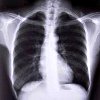

Рентгеноскопия легких

Рентгенография легких в травматологии показана при подозрении на гемоторакс или пневмоторакс при переломах ребер. В отличие от обычной рентгенографии, которая позволяет получать изображения на пленке, исследование позволяет увидеть исследуемый орган на специальном рентгеноскопическом экране. С помощью рентгеноскопии легких обследующий врач просит пациента задержать дыхание, вдох Эти простые тесты помогают рентгенологу оценить движение диафрагмы и изменения в ткани легких, которые происходят во время дыхания. Существенным недостатком рентгеноскопии легких является большая доза облучения пациента, чем при рентгенографии.

Во время исследования изображение исследуемого органа формируется не на пленке, как при обычной рентгенографии, а на специальном экране. Рентген проходит через тело пациента и попадает на экран. Интенсивность свечения зависит от плотности ткани, пройденной лучами. Врач видит изображения органов в режиме реального времени. Преимуществом флюороскопии является возможность исследовать орган во время его работы. Во время легочной радиоскопии рентгенолог может оценить движение легких и движение диафрагмы непосредственно во время дыхательных движений.

Недостатком этого метода является то, что полученные изображения не могут быть записаны на пленку, что препятствует дальнейшему обсуждению объективных данных с другими специалистами. Радиационная нагрузка на пациента и врача при флюороскопии выше, чем при рентгенографии. Кроме того, на рентгеновском экране мелкие детали изображения четко не видны.